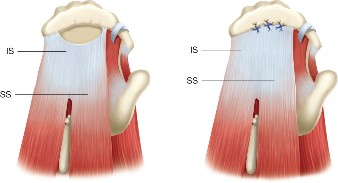

The correct answer is (E). Given that her rotator cuff has atrophied and has fatty infiltration to the point where there are equal parts fat and muscle, this is considered an irreparable rotator cuff tear. Repair should not be attempted because of poor outcomes following repair (see last two paragraphs of this discussion below). A reverse total shoulder arthroplasty is an alternative to repair that should be used in cases of massive, irreparable rotator cuff tears. It is a semi-constrained prosthesis that restores function in patients with massive rotator cuff tears by constraining a concave humeral cap inferior to a semispherical glenoid component (glenosphere). This creates an inferior force-couple and a fulcrum that replaces the stabilizing function of the infraspinatus maintaining a center of rotation around which the shoulder can move. This allows the deltoid to abduct and flex the shoulder without causing the humerus to migrate superiorly and about the acromion. In an elderly patient with a massive, irreparable rotator cuff tear (as in this patient), a reverse total shoulder arthroplasty is the procedure of choice.

This classification was originally based on CT imaging but is now applied to MRI imaging and uses sagittal oblique views at the most lateral slice in which the scapular spine is continuous with the scapular body. There are five categories that range from stage 0 to stage 4. A classification of stage 0 is normal, stage 1 is some fatty streaks, stage 2 is more muscle than fat, stage 3 is equal amounts of fat and muscle, and stage 4 is more fat than muscle. This patient’s rotator cuff tear involves the supraspinatus and infraspinatus, and both have atrophied to the point of having equal amounts of fat and muscle, giving her tear a Goutallier classification of stage 3 (see Table 2–2 and Fig. 2–18). As a general rule, if there is stage 3 or 4 fatty atrophy, rotator cuff repair will not be successful and a reverse total shoulder or tendon transfer would be a better operation.

Figure 2–18_Three different patients showing different stages of fatty degeneration with Goutallier stages. Higher stages are predictive of worse outcomes after rotator cuff repair. SS, supraspinatus; IS, infraspinatus; TM, teres minor; Sub, subscapularis. (From Kuzel BR, Grindel S, Papandrea R, Ziegler D. Fatty infiltration and rotator cuff atrophy. _J Am Acad Orthop Surg. 2013;21(10):613–623.)

The correct answer is (A). In young, active patients with a massive, irreparable rotator cuff tear without glenohumeral arthritis, a tendon transfer is the most reasonable option to attempt to restore function of the shoulder. In a tear involving the supraspinatus and infraspinatus, the posterior and inferior force-couples in the transaxial and coronal planes, respectively, are out of balance because of the involvement of the infraspinatus in both of those. Because of this, the humerus cannot be dynamically stabilized in the glenoid during active movement of the shoulder. The most popular way to restore this in a young, healthy patient is through a latissimus dorsi tendon transfer in which the insertion of the tendon is transferred from the humeral shaft to the greater tuberosity (see Fig. 2–19). This creates a new posterior and inferior force-couple and creates an external rotation force.